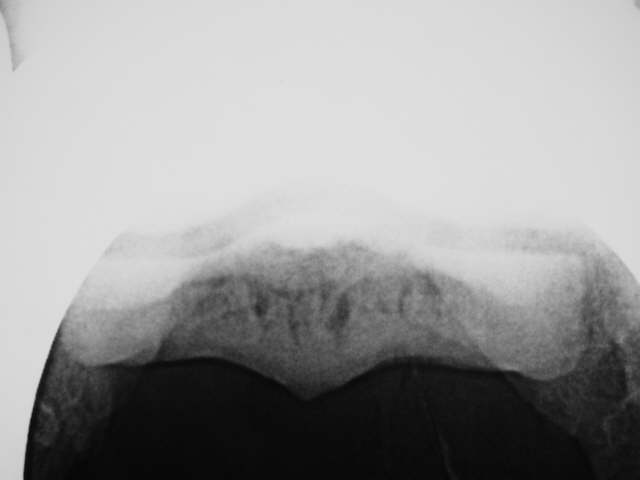

Skyline Befunde

Starke Zunahme der Dicke der Knochenschale, Verlust der feinen Knochenstruktur im Markraum und ungleichmäßige Oberfläche der Gleitfläche der tiefen Beugesehne. Röntgenklasse IV